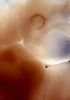

Carnegie Stage 16 (37 post-ovulatory days)

Most embryos at stage 16 are approximately 37 postovulatory days old and measure 11-14 mm in length. Distinguishing criteria for this stage include the external appearance of retinal pigment, the nasal pits face ventrally, pharyngeal arch 2 is more massive and conspicuous than arch 3, auricular bumps begin to appear, and the thigh, leg, and foot can be distinguished in the lower limb.